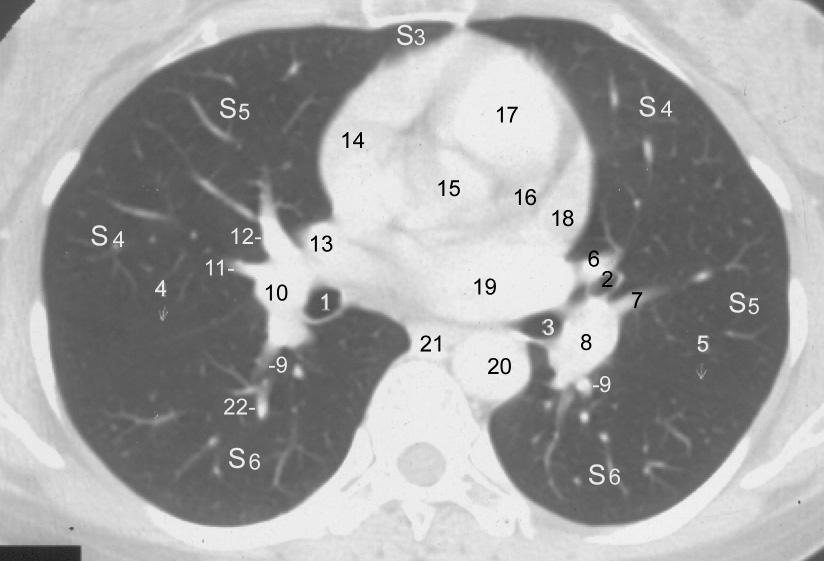

②断层解剖学。上面已经提到了系统解剖,跟这个有什么区别呢?区别大了,简单说,系统解剖就是把人剖开看看里面完整的器官是怎么样的(啊…和谐…),而断层解剖就是把人切成一片一片(啊……一定要和谐……)看看每一片里有什么。难度可想而知。看到这里大家一定明白了,没错,这一片,就是片子上的那一片。

为什么学习这门课?这样,每一层,你才能看出来到底哪里出了问题。一张片子,医生看到的远比你们想象中看到的东西要多的多,这一片灰度相同的的区域,其实医生知道那绝不是一个东西。

下面就是CT。X线的扫描等于把人体压成一张薄薄的纸来观察,但是只有一个方向,CT就是把人切成一个个薄片,相当于多层的X线扫描。可以把人切成1cm 的薄片,也可以切成0.5cm。越薄精确度就越大。再举个简单的例子,人体的肿瘤就像在馒头里藏了一颗沙子。X线可以看穿馒头,发现沙子,但是仅仅是平面效果。也就是仅仅在一个平面上,只知道在馒头中间有沙子,并不知道在馒头里面多深的位置。这时候就需要CT,比如说0.5cm的扫描,就相当于把馒头间隔0.5cm切片,把每一片拿出来找这颗沙子。这时候,稍微大点的沙子都可以被发现。而且可以确定在多深的位置。但是如果是更小的沙子就,刚好在0.5cm的两层之间,也可能不会被发现。